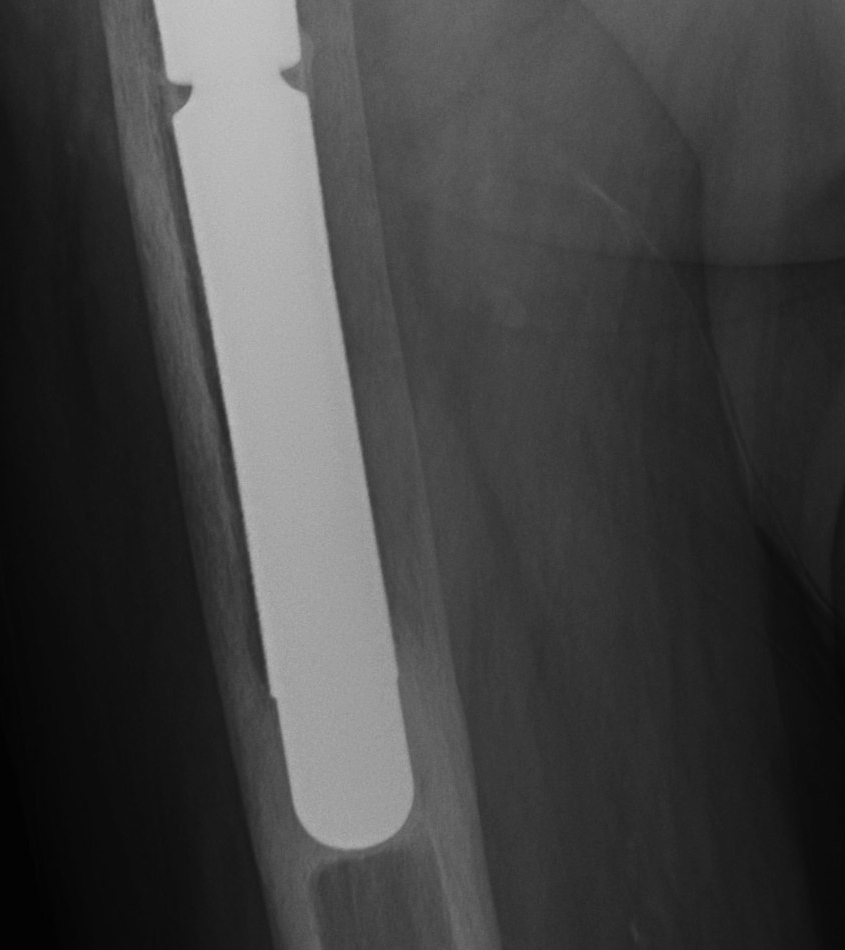

Xray

- distal cortical hypertrophy

Stress shielding

Fully coated / diaphyseal fit prostheses

Stress shielding

Loosening

Lucent lines

Signs of frank implant instability

- component migration - subsidence and varus tilt

- progressive luceny on serial radiographs

- development of inferior pedestal

Stem migration Pedestal